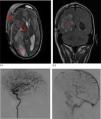

Varón con shock séptico de partes blandas por Streptococcus pyogenes tras traumatismo. Diseminación hematógena con fascitis necrosante en extremidades (resección quirúrgica) y meningitis con absceso cerebral (craniectomía y evacuación). Tomografía (TAC) con contraste: edema en el tejido subcutáneo del brazo izquierdo y en los vientres musculares, y colección en la cara medial de la pierna derecha (fig. 1, flecha azul). Hematoma craneal lobar parietooccipital derecho, edema vasogénico y hemorragia subaracnoidea traumática en cisternas, con aumento del efecto masa (borramiento de surcos y compresión del ventrículo lateral derecho) (fig. 2, recuadro naranja). Resonancia craneal tras empeoramiento clínico (fig. 3): colección occipitotemporal derecha de 3,5×9cm, márgenes irregulares hipercaptantes y restricción (estrellas rojas) sugestiva de absceso cerebral, con pus intraventricular, herniación subfalciana y uncal derecha (flechas rojas), así como hematoma subdural a nivel de la craniectomía (triángulo rojo).